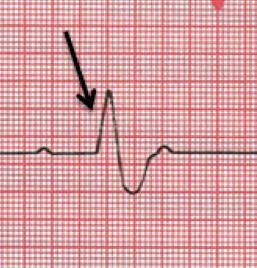

Which statement describes the condition of the heart at the point indicated in the electrocardiogram?

The muscles of the ventricles depolarize.

An electrocardiogram, often known as an ECG, is a test that aids in calculating and graphing the electrical activity of the heartbeat. Every time the heart beats, a wave or electrical impulse travels through the organ, causing the muscles to contract and the blood to be pumped from the heart's chambers. Ventricular Depolarization physically occurs in the heart with QRS Complex.